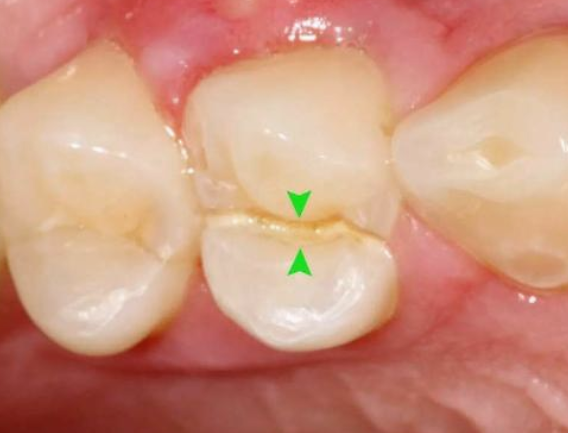

真實(shí)案例:下面這幅圖片就是一個牙科醫(yī)生發(fā)出來的一個患者的牙,之前做了“根管治療”后,沒有及時做“牙冠”,導(dǎo)致吃東西時把原來做過‘根管治療’的牙直接劈成了2半,這不是既麻煩又難受?后悔都來不及了!!